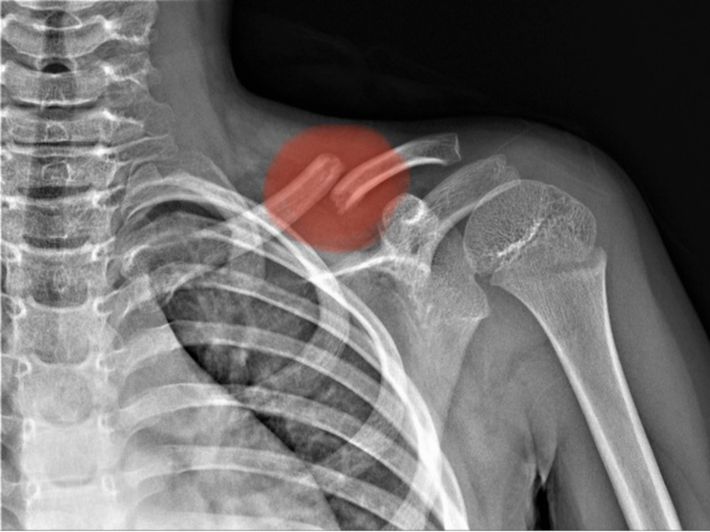

أماكن كسر عظام الترقوة

ويحدث كسر الترقوة في إحدى العظمتين الطويلتين الرقيقتين اللتين تربطان عظم القص بالكتف، وبناءً على ما نشره الموقع الطبي "webmd"، هناك ثلاثة أنواع من كسور الترقوة:

في منتصف عظم الترقوة بين عظم القص ومفصل الكتف.

وأيضاً يمكن أن يكون الكسر بالقرب من مفصل الكتف.

أو يكون الكسر بالقرب من عظم القص (وهو أقل أنواع كسر الترقوة شيوعًا).